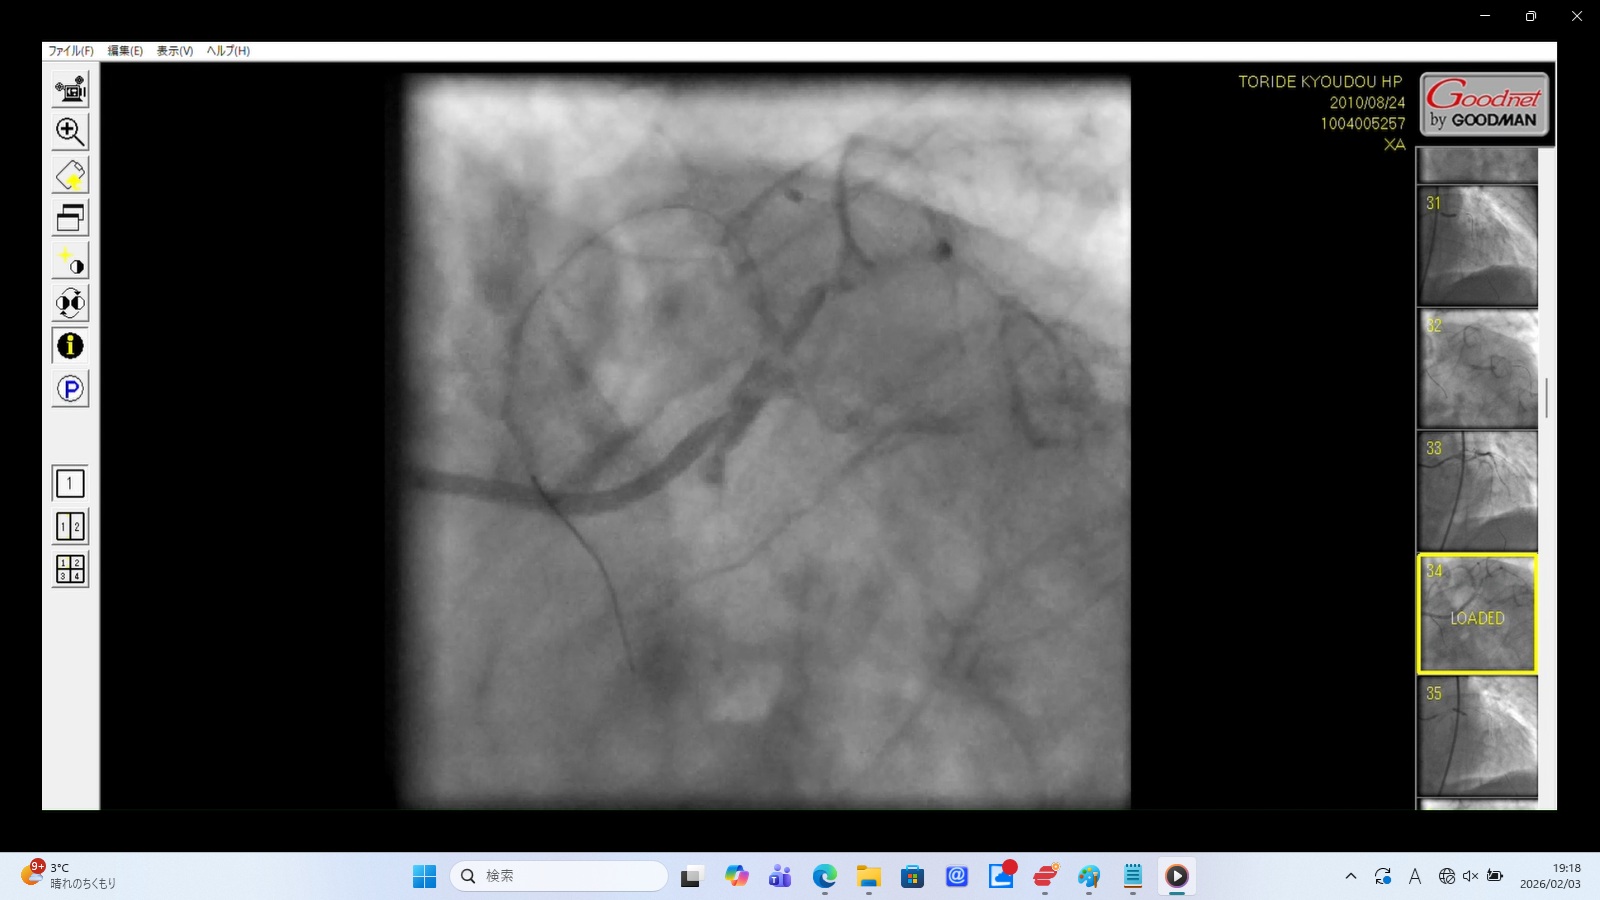

LMTの偽腔: 左冠動脈主幹部が二股に分かれ、造影剤への染まりが悪い。これは真腔と偽腔が併存している状態(重度の解離)を示している。

大動脈への押し戻しと漏出: 造影剤が血管内に入りきれずに大動脈へ逆流すると同時に、解離した血管壁の損傷部位から血管外(心嚢方向)へ漏出。